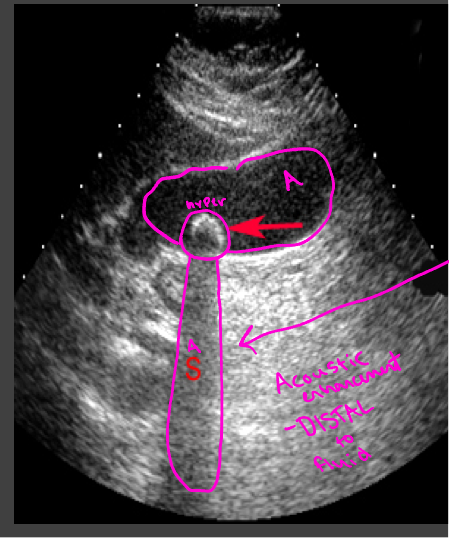

Echogenicity

Level of gray or brightness on an ultrasound image

Described in relation to surrounding tissues

Isoechoic

Uniform in color

Liver

Hypoechoic

abscesses, fatty tissue

Darker = less echoes

Hyperechoic

Bone, kidney/gallbladder stone

lighter = more echoes

Anechoic

no echos

Bladder, cystic fluid, gallbladder

Artifacts-enhancement

Acoustic enhancement- sound travels through fluid uninterrupted, so the echoes deep to a fluid collection are brighter than the adjacent tissue

In poorly attenuating objects such as a cyst, the echoes returning from regions deep to the object are of higher amplitude

Artifacts- shadowing

A structure that blocks the sound wave causes acoustic shadowing (gallstones)

Strongly attenuating or highly reflective surface, the returning echoes posterior to the structure are decreased in amplitude